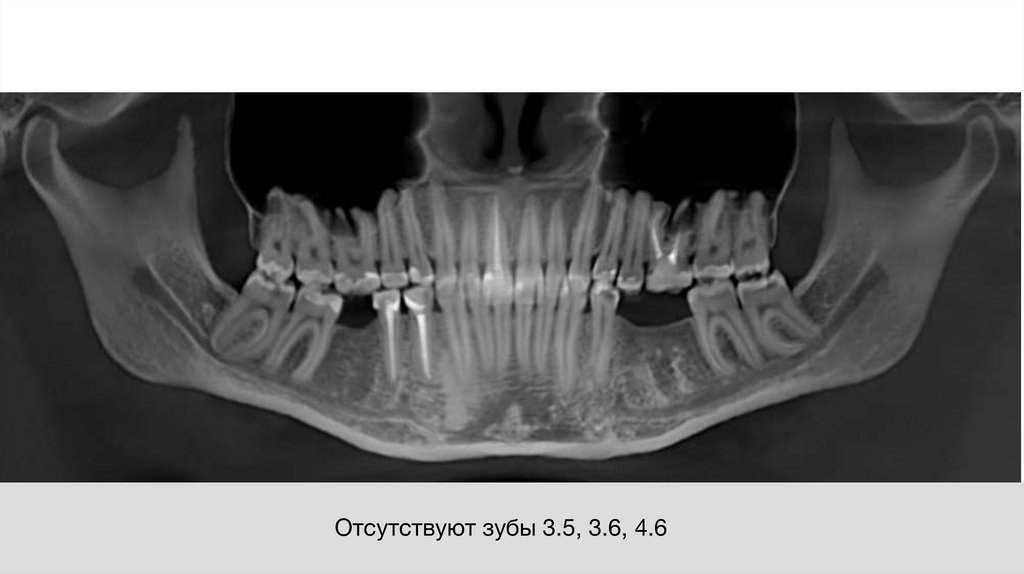

Отсутствуют зубы 3.5, 3.6, 4.6

17. Отсутствуют зубы 3.5, 3.6, 4.6

• Отсутствие зубов 3.5, 3.6, 4.6